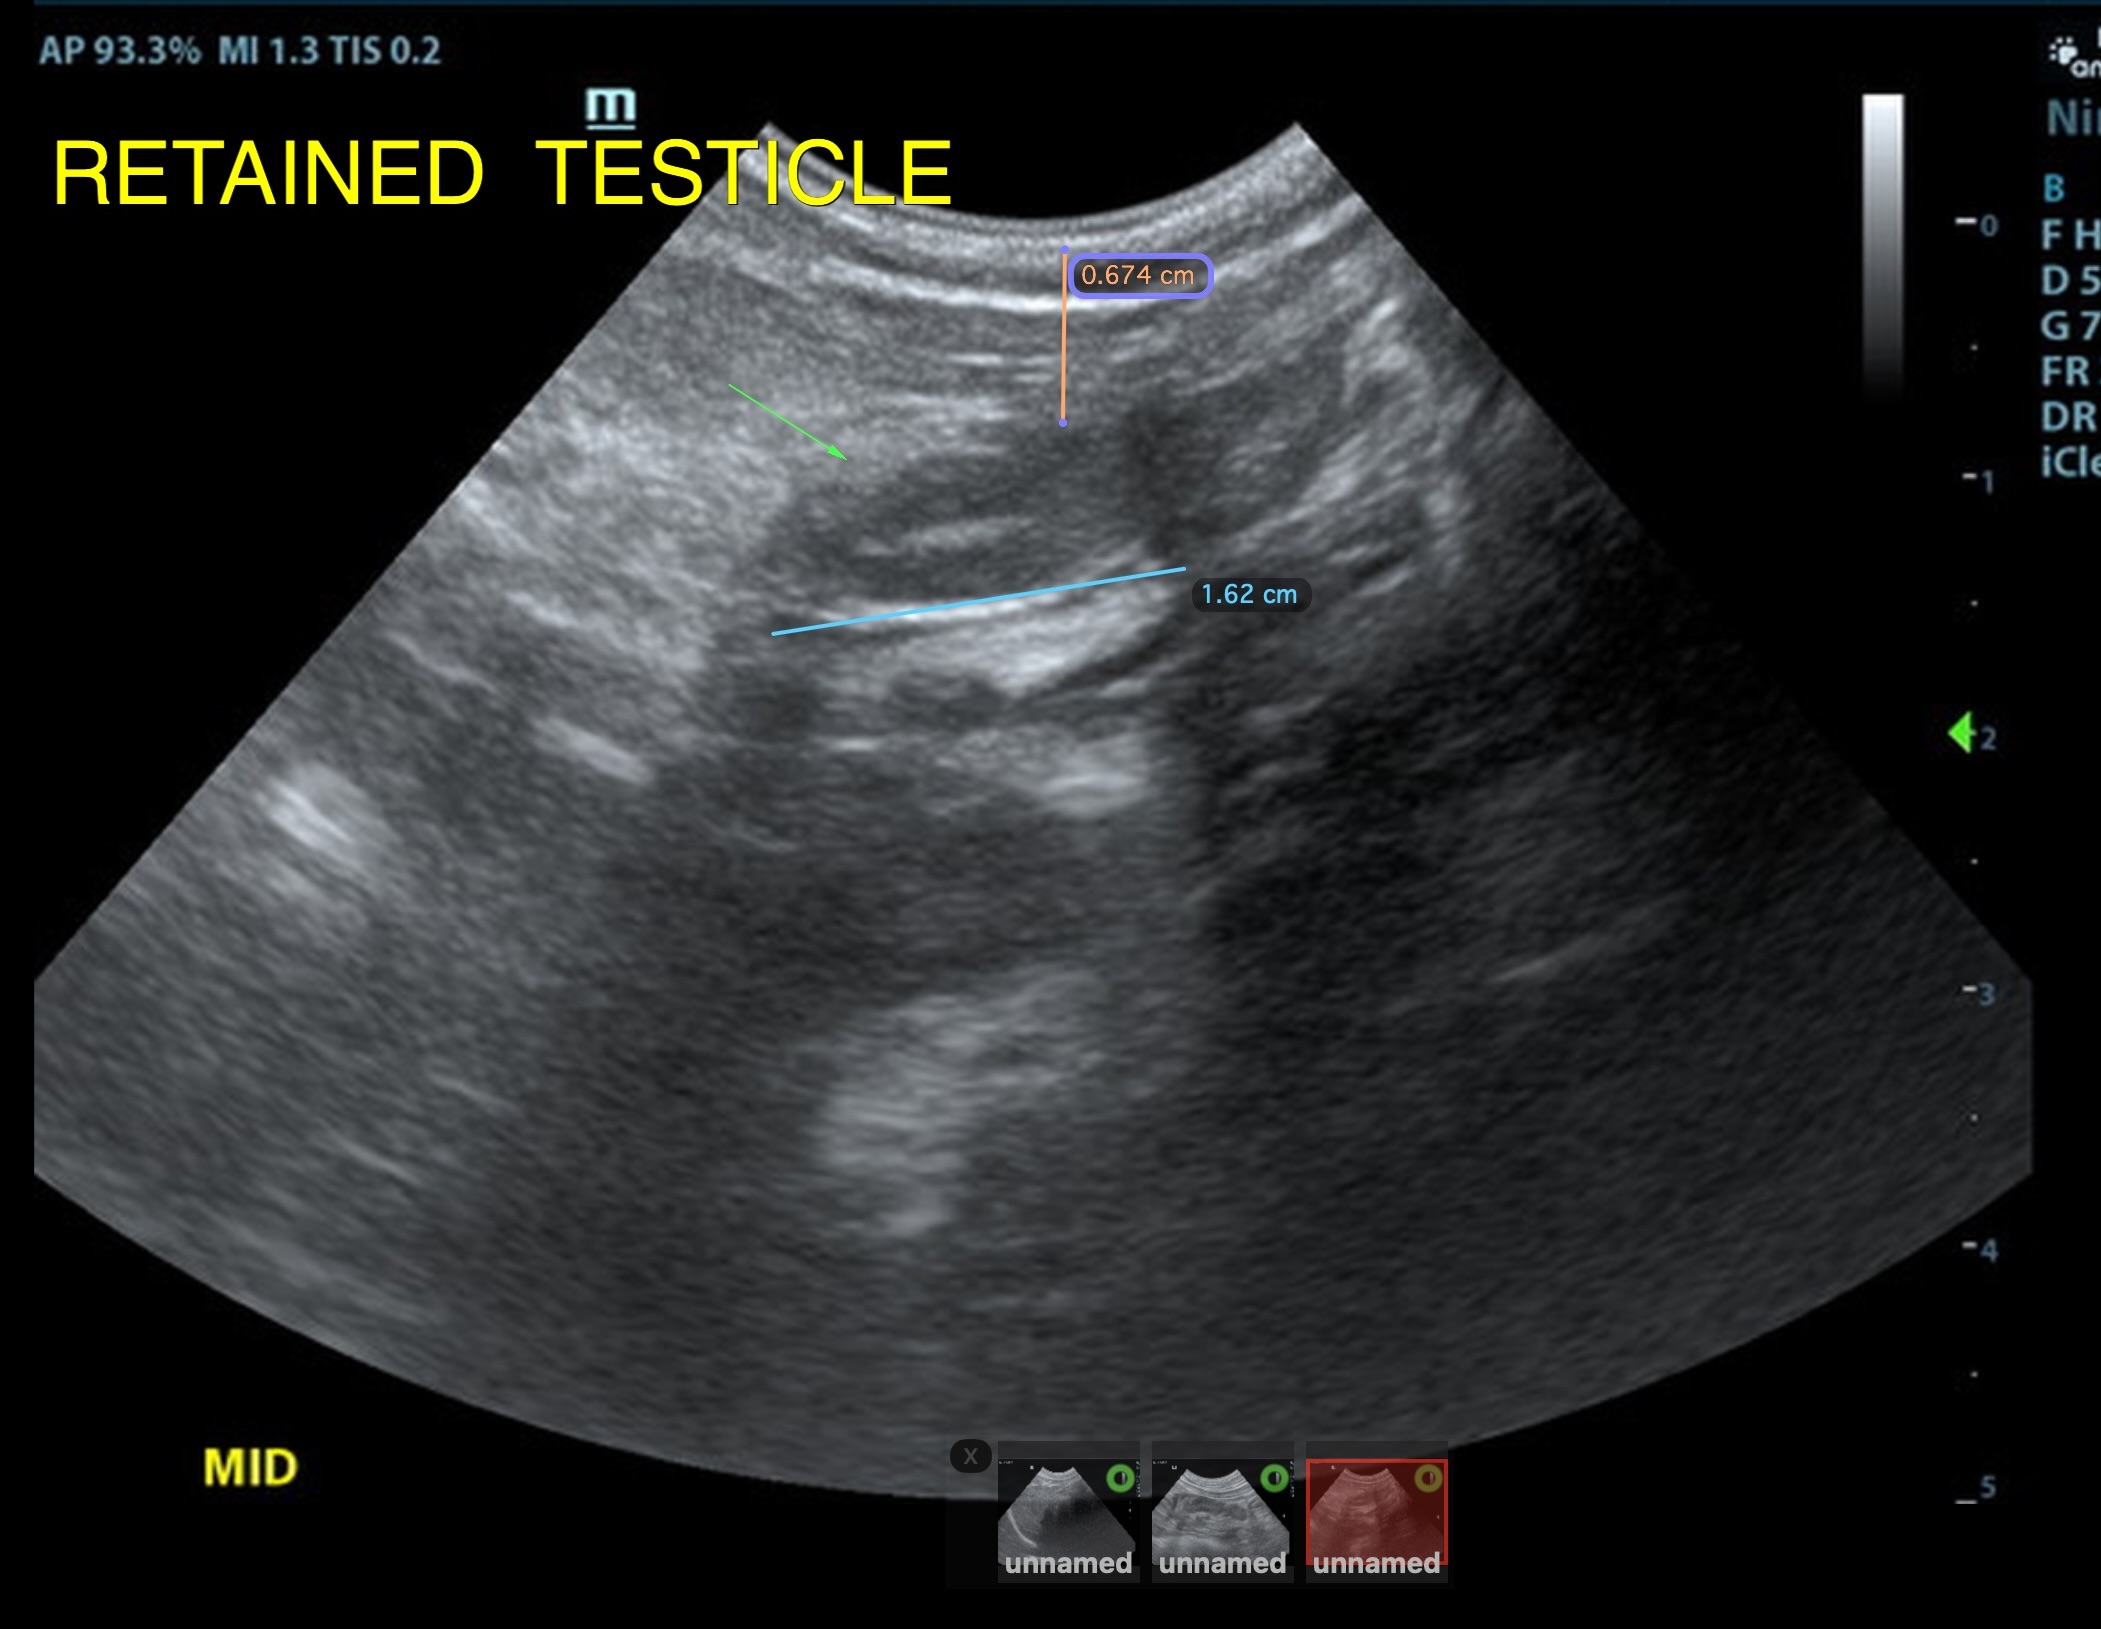

The retained testicle in this patient was midline subcutaneous inginal position, measuring approximately 1.6 cm in length and at a depth of 0.67 cm, approximately 2.0cm caudal from the cystourethral junction of the bladder. The left descended testicle was normal, measuring 1.8 cm

retained right testicle midline subcutaneous inguinal position

Orchiectomy is recommended with right inguinal incision for the retained testicle